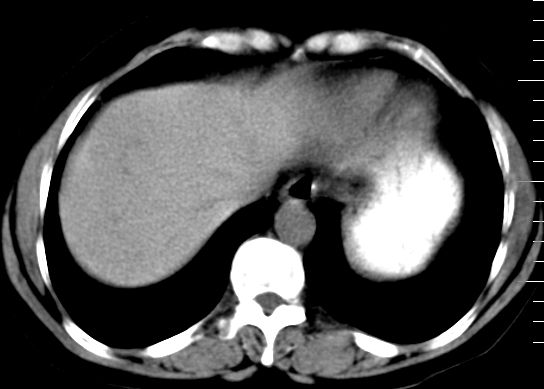

肝大小形态未见异常,肝内外胆管无扩张,肝s8段见一动脉期明显血管样强化结节,门脉期呈高密度,延迟期呈等密度,胆囊不大,增强扫描见胆囊及胆囊颈管壁增厚,有强化。

1、胆囊炎(轻度)。

2、肝s8段结节,考虑小血管瘤。

3、左肾下极低密度灶,考虑囊肿可能性大,建议随访,除外小肾癌(无强化可以基本除外)。

4、目前ct表现尚不能解释患者上腹部疼痛,建议上消造影检查,除外胃炎等疾患。